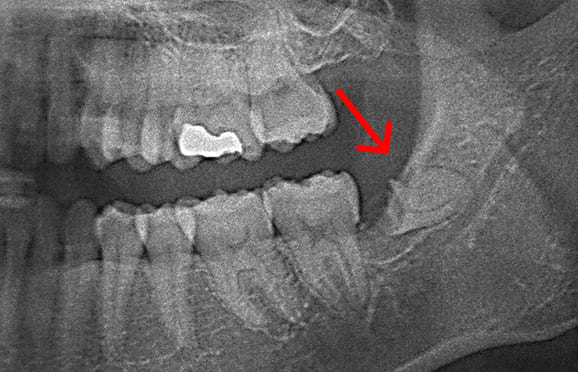

01 神経に近い位置に親知らずの根が存在

02 親知らずの頭の部分だけ抜歯

03 親知らずの根の部分が神経から離れる

下の顎の親知らずの抜歯では、神経の損傷リスクを考えて2回に分けて抜歯する場合があります。 また、麻酔が効きにくい場合にも、同様に2回に分けて抜歯します。